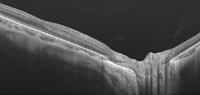

Figura 5)

7. El desarrollo de estos sistemas hará que la ayuda proporcionada por la OCT intraoperatoria sea cada vez mayor, y caben esperar mejoras en los próximos años tanto en lo que respecta a las pantallas de visualización de imágenes de OCT integradas en los microscopios como en el desarrollo de instrumentos quirúrgicos específicos, con propiedades ópticas determinadas que produzcan una disminución de la sombra posterior en las imágenes de OCT.

Figura 5. OCT intraoperatoria con sistema de autofoco eléctrico y tecnología en-face. La superficie del pincel de pelado aparece codificada en rojo y la membrana limitante de la retina en verde en las imágenes de OCT (arriba y derecha). La diferencia de posición axial entre ambas estructuras permite obtener una medida de la distancia entre el instrumento y la retina, y con ayuda de la tecnología en-face se representa en un código de colores visible en el propio instrumento, ofreciendo esta información al cirujano durante el pelado y facilitando las maniobras quirúrgicas (izquierda). (Fuente: Tao YK, Srivastava SK, Ehlers JP. Microscope-integrated intraoperative OCT with electrically tunable focus and heads-up display for imaging of ophthalmic surgical maneuvers. Biomedical Optics Express. 2014;5(6):1877-85).